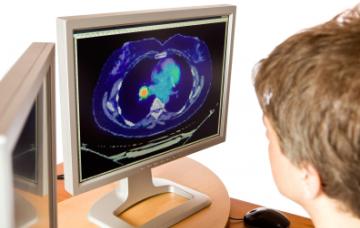

Diagnóstico del cáncer de pulmón

Un diagnóstico temprano del cáncer de pulmón puede evitar que se haya extendido y resulte incurable. Conoce las pruebas que permiten detectarlo.